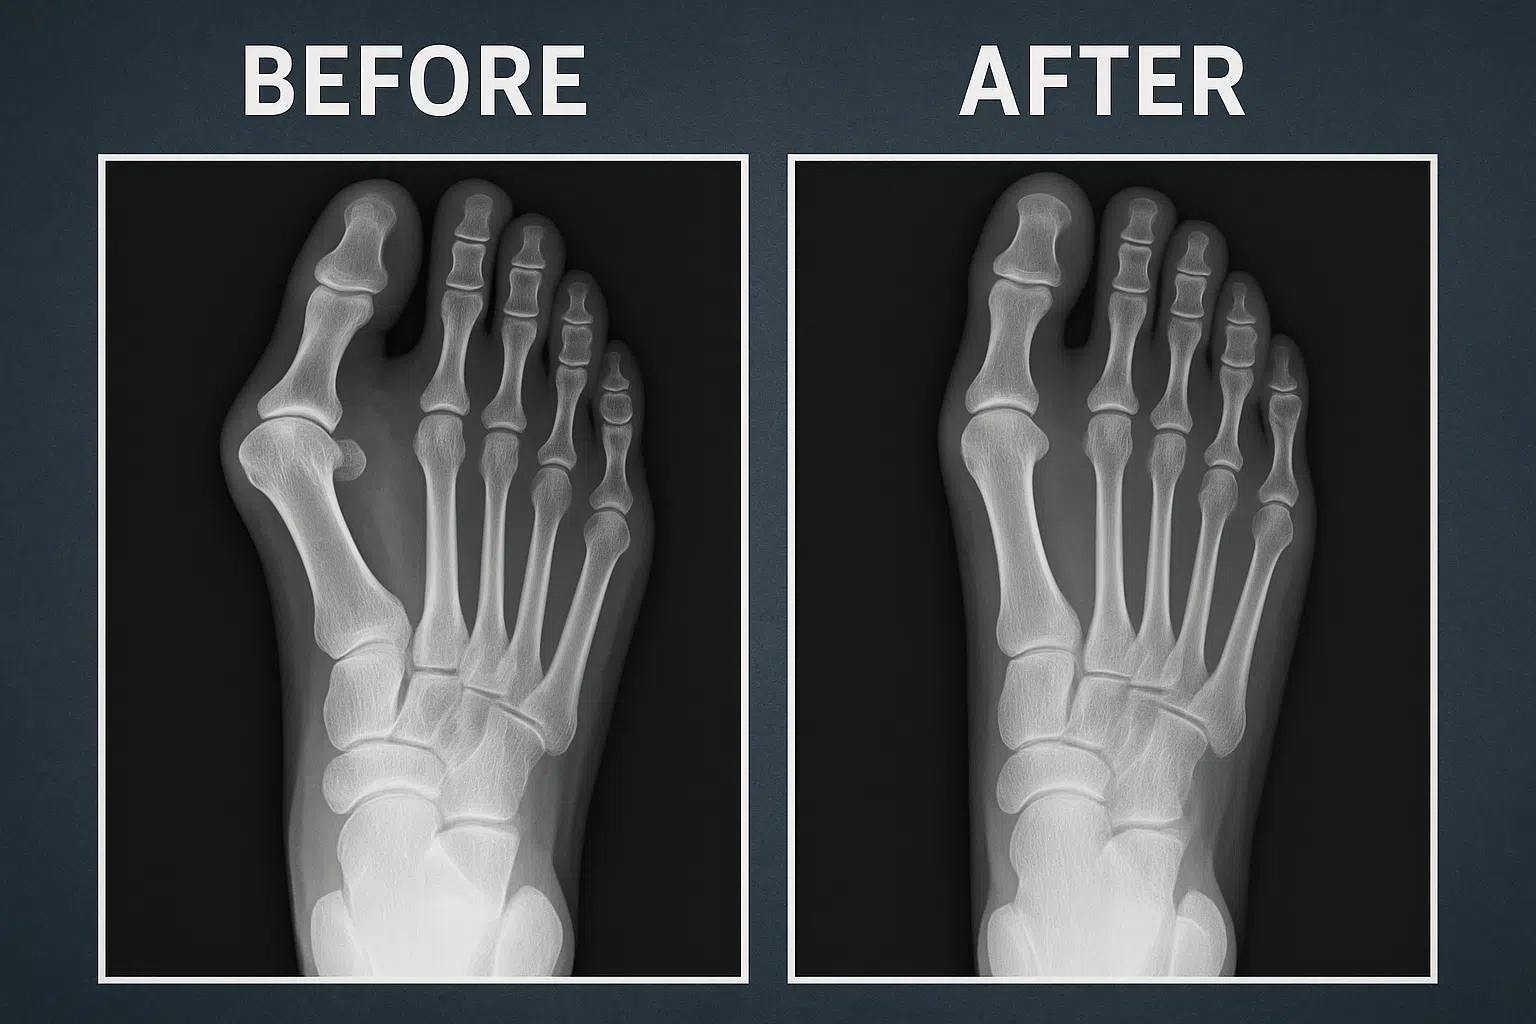

환자의 직업이나 운동 습관, 기저질환을 확인하고 관절의 가동 범위와 신경 촉발음을 검사합니다. X-ray 검사를 통해서는 골극이나 골절을 확인할 수 있으며, 초음파 검사로는 힘줄이나 활액낭의 염증을 확인할 수 있습니다. MRI 검사는 연부조직을 세밀하게 평가하고 심부 감염이나 종양을 확인하는 데 유용하며, 혈액이나 관절액 검사를 통해서는 요산 수치, 자가항체, 염증 수치 등을 확인할 수 있습니다.

먼저 신발이나 인솔을 교정하여 발가락에 가해지는 부하를 감소시키고, 냉찜질이나 온찜질, 소염진통제, 국소 스테로이드 주사 등을 활용할 수 있습니다. 수건을 이용한 스트레칭이나 테니스공 굴리기와 같은 근력 운동도 도움이 됩니다. 중등도 이상의 변형이 있을 경우에는 Chevron 절골술이나 관절 성형술 등의 수술적 치료를 고려해볼 수 있습니다. 통풍의 경우 요산 저하 약물과 함께 식습관 교정이 필요하며, 류마티스 관절염의 경우 DMARDs를 꾸준히 복용해야 합니다.

보존적 치료를 6개월 이상 시행했음에도 반응이 없다면 교정 절골술이나 관절 유합술을 최종 선택지로 고려할 수 있습니다.